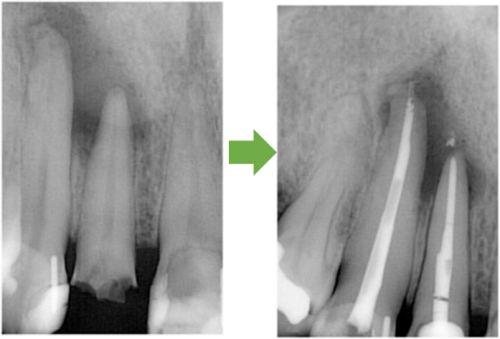

歯髄壊死 左上の前歯 川口の歯科 歯医者 さかえ歯科クリニック

2014年12月16日

術 前 術 後